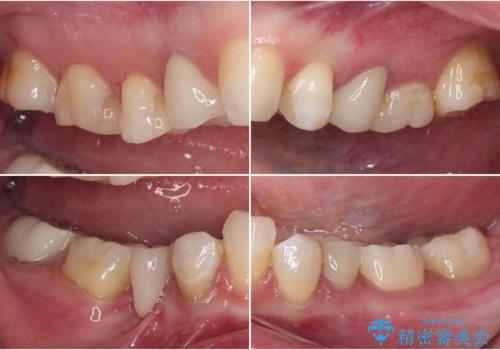

- クラウンから金属の土台が見えてきてしまったとのことで、作り替えを希望して来院された患者様です。

前歯や金属が露出している歯、痛みを感じる歯を中心に、オールセラミッククラウンにて補綴治療することとしました。

以前はセラミッククラウンのフレームとして金属が使用されており、歯肉の経年変化やセラミックのすり減りなどにより、金属が見えるようになってくることがあります。

現在は金属の代わりに強化セラミックを使用したオールセラミッククラウンが主流です。金属色が気になる方はご相談ください。